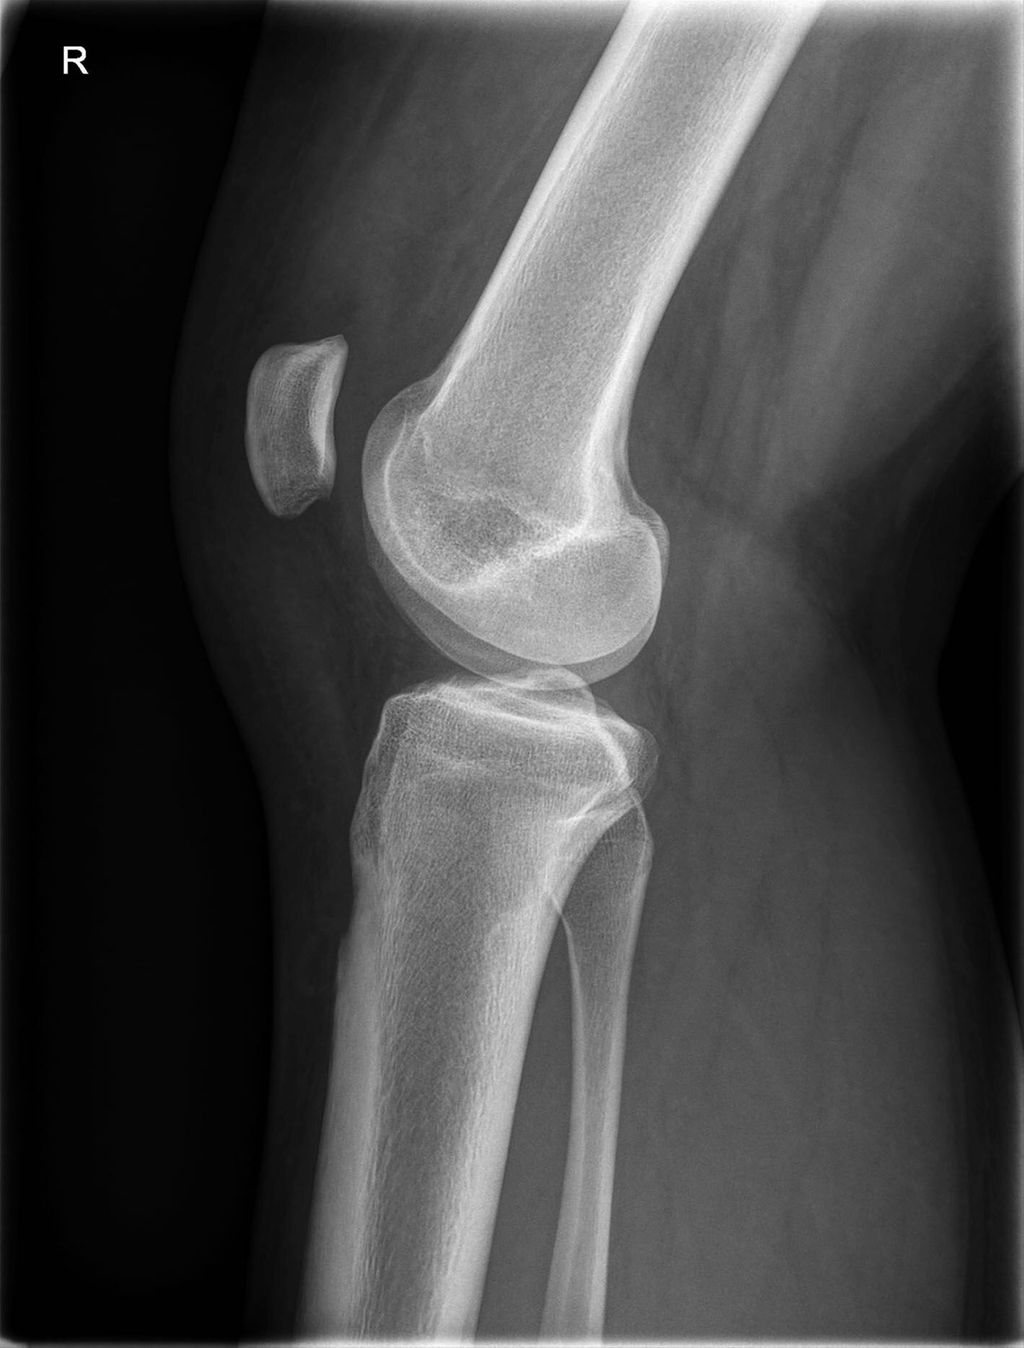

Fallbeispiel

23-jähriger Patient mit wiederkehrenden Patellaluxationen und vermehrtem Valgus von ca. 6,5% (Abb. 6) und einer Trochleadysplasie

Geplant wurde eine lateral aufklappende Femurosteotomie (Abb. 7) mit offener Trochleaplastik und MPFL-Plastik. Bei der Umstellung kam es zu einer iatrogenen Verletzung der A. poplitea. Diese musste durch einen Gefäßchirurgen mit einem Venenbypass (Vena saphena magna) behandelt werden, zusätzlich wurden die Unterschenkelkompartimente gespalten (Abb. 8).

Abb. 8: Zustand nach iatrogener Verletzung der A. poplitea mit Venenbypass und Kompartimentspaltung